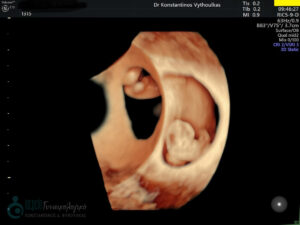

- Υπερηχογραφική εξέταση, η οποία συμβάλλει στη διαπίστωση της ενδομήτριας κύησης και αποκλεισμό της έκτοπης κύησης. Επιπλέον, μπορεί να διαπιστώσει εάν πρόκειται για μονήρη ή πολύδυμη κύηση, να ανιχνεύσει την εμβρυϊκή καρδιακή λειτουργία μετά τις 6 εβδομάδες και να προσδιορίσει υπερηχογραφικά την ηλικία κύησης, με βάση το κεφαλουραίο μήκος του εμβρύου μετά τις 8 εβδομάδες.